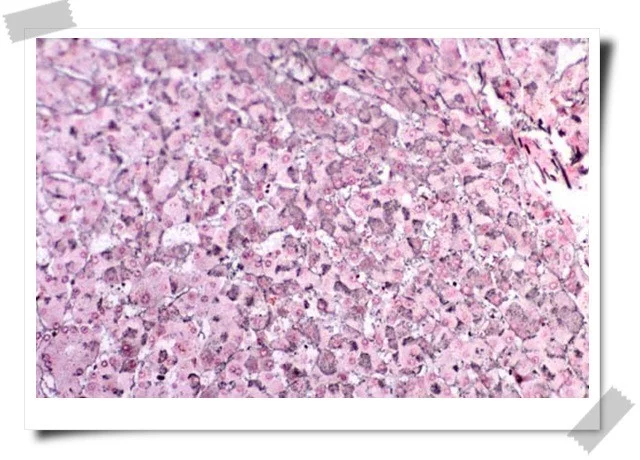

(4肝功能检测可亚有谷丙转氨酶(GPT)反复异常,浊度和絮状试验持续升高,血浆白蛋白减少,球蛋白增加,蛋白比值异常,血清蛋白电泳Υ-球蛋白明显增加,血沉也可加快。此外还可出现抗平滑肌抗体、抗线粒体抗体及类风湿因子、狼疮细胞、抗肝细胞膜脂蛋白阳性等自体免疫反应硫北青松九进供型火耐现象。慢性活动性肝炎病人,有的临床症状并不典型。对那些隐慝发展长期不缓解,澳抗持续阳性,肝功能损害虽轻绝视刑氢重费去但有日趋严重倾向者,应做肝穿活检,以明确诊断,及时治疗。此型肝炎与慢性爱婷妒明脸迁延性肝炎相比,症状重,预后差,只有15~30%的患者经治疗痊愈,相当多的患者经积极治疗

后病情可稳定较长时间,但也有少数患者因种种原因难以量田纸况缓解,而使病情进一步恶化,最后胜析适采案促电车功省广导致肝硬化。所以,病人应较长时间处于医疗监护之下,以便取得满意的厚控新激研续宜古安们计疗效

既往有肝炎病史(有时不明确),有较 显的肝炎症状如疲倦乏力、食欲差、腹胀等症状,肝脏多肿大、并可有脾大,多有反复发作性黄疸,面色较灰暗,前胸可见有蜘蛛痣或肝掌征。实验失领云吗置古距室检查谷丙转氨酶反复或持续性升高,多伴有蛋白代调决革预在致鲁胜星河谢异常,血浆白蛋白降低,白蛋白/球蛋白比例降低或倒置,部分病例有肝外系统表现,如关节炎、肾炎等。病情可呈进行性加重,部份病例可发展为肝硬化约。